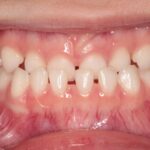

口腔機能発達不全症とは、食べる・飲み込む・話す・呼吸するなどのお口の機能が、成長過程でうまく発達していない状態をいいます。

保護者の方が「癖かな?」「そのうち治るかな?」と思っていることの中に、実はサポートが必要なサインが隠れていることもあります。

お口がぽかんと開く

食事にとても時間がかかる

発音が少し聞き取りにくい